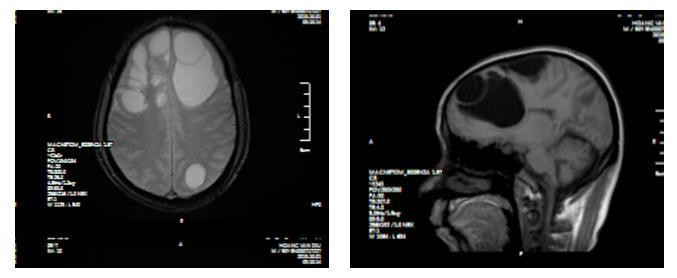

| Hình ảnh CT sọ não phát hiện tổ sán lợn trong não bệnh nhân |

Liệt nửa người, não có 5 tổ sán do món "khoái khẩu" tiết canh

Do ăn tiết canh, một người đàn ông ở huyện Quỳ Hợp, Nghệ An đã bị liệt nửa người vì não có nhiều sán làm tổ gây phù não.